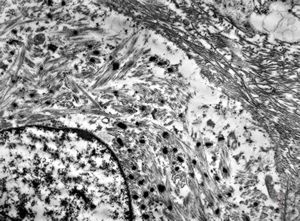

M,56y. | amyloidosis - tendon